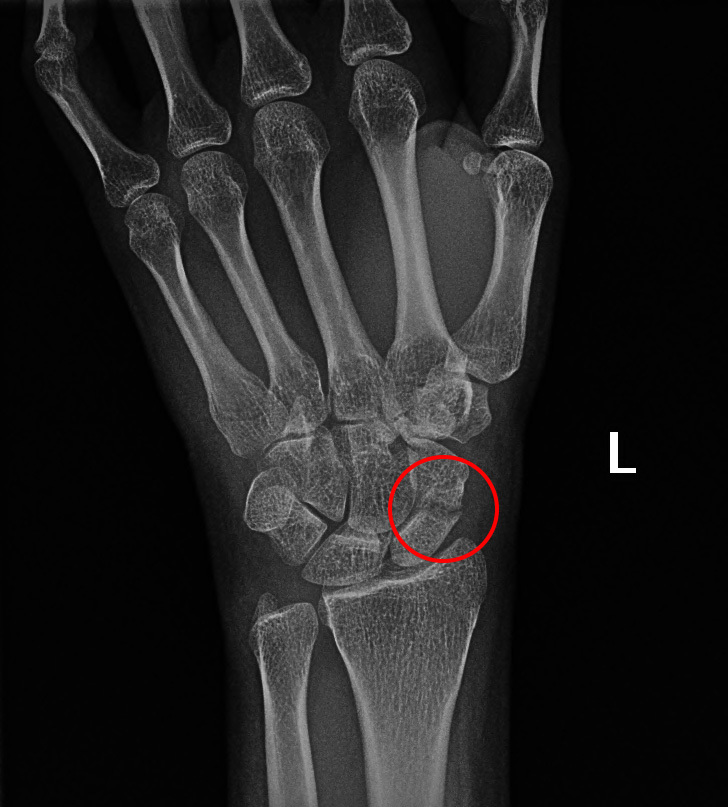

Scaphoid fracture